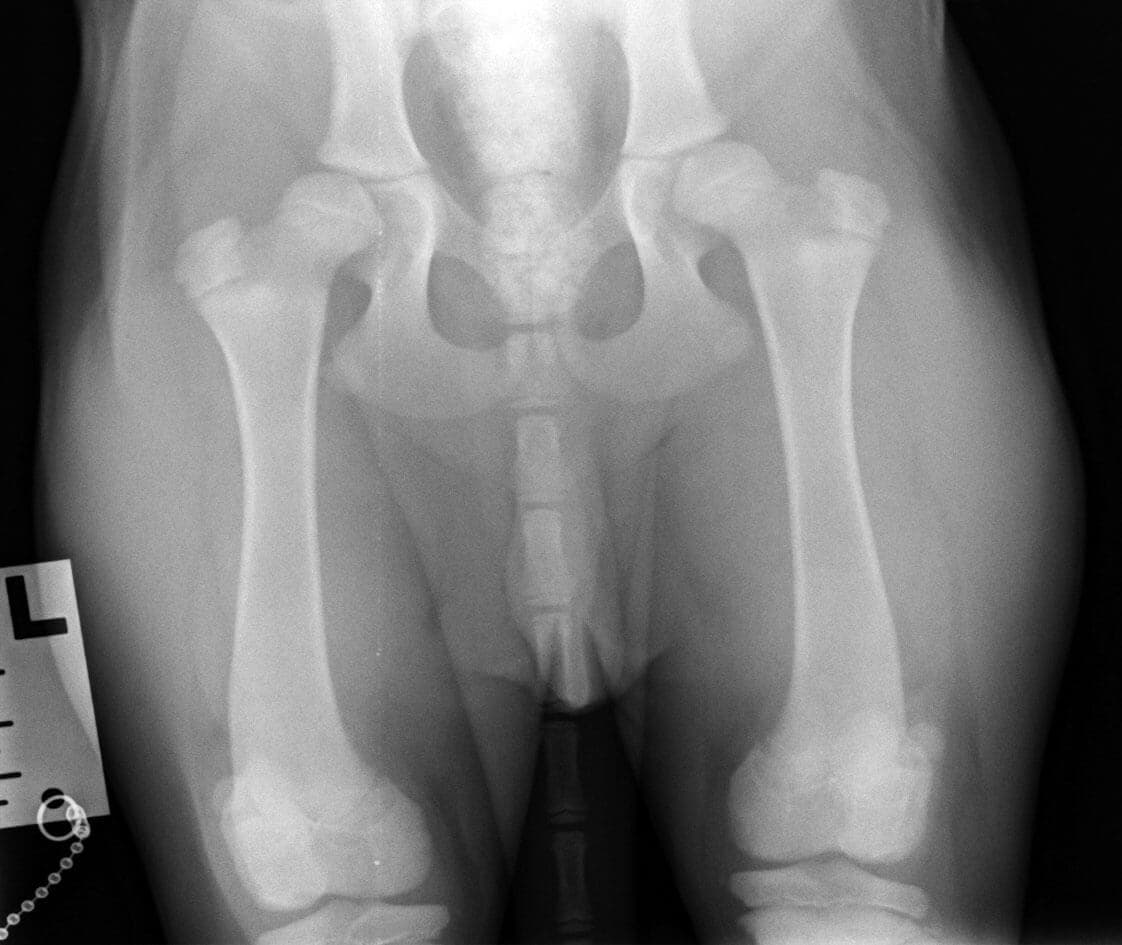

ПРИМЕР ОБСЛЕДОВАНИЯ НА ВЕРОЯТНОСТЬ РАЗВИТИЯ ОСТЕОАРТРОЗА В 4 МЕСЯЦА.

Щенок лабрадора 4 мес. Уже на проекции “лежа на спине с вытянутыми ногами” видно недостаточное покрытие головок бедренной кости крышей вертлужной впадины.

На снимке “дистракционная проекция” виден значительный выход головки бедренной кости из вертлужной впадины, что говорит о значительной вероятности развития остеоартроза в ближайшие годы жизни животного.